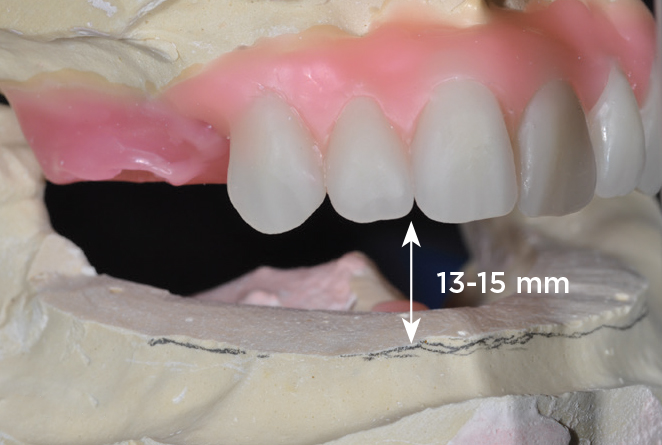

An important advantage of this approach is the ability to simulate bone reduction on the models and verify the presence of 15 mm to 17 mm and 13 mm to 15 mm of required inter-occlusal space for maxillary and mandibular restorations, respectively. This creates a platform for a diagnostic wax-up of the proposed dental rehabilitation and fabrication of wax prosthesis try-ins when necessary. Finally, a modified All-on-4 provisional prosthesis surgical and restorative guide developed by the authors for restoration-driven surgery and simplified restorative procedures is fabricated (Figure 2 through Figure 8).

Fig 4. Diagnostic wax-up performed after model surgery simulating maxillary tooth extraction. Note that inferior repositioning of the incisal plane helped create the 15 mm to 17 mm inter-occlusal space needed for the maxillary All-on-4 provisional restoration.

Figure 4

Fig 5. Bone reduction model surgery performed in mandibular arch to create 13 mm to 15 mm of inter-occlusal space required for the mandibular All-on-4 provisional restoration.

Figure 5